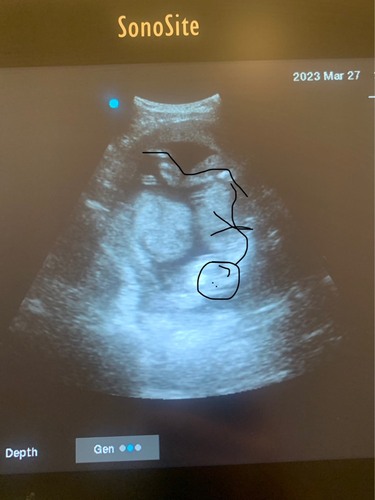

Een echo onderzoek is een dynamisch onderzoek, dus met 1 plaatje kan je weinig. Het lijkt me minder waarschijnlijk dat het een cyste is want daar zit meestal vocht in (= zwart op echo). Ik zou je verloskundige vragen als je je zorgen maakt.

Heel vaag beeld sowieso... Ik zou ook de verloskundige bellen en niet meer zelf echo's maken.. ^^'

Zit er niet per ongeluk een darmlis voor je beeld? Op een enkel plaatje is dit nauwelijks te beoordelen

Ze zegt dat dat het hoofd is, maar ik vind dat toch wel een gekke hoek om het hoofdje te zijn of wat denken jullie 馃

Geloof nou gewoon je verloskundige! Geen zorgen maken en geen echo meer zelf maken!